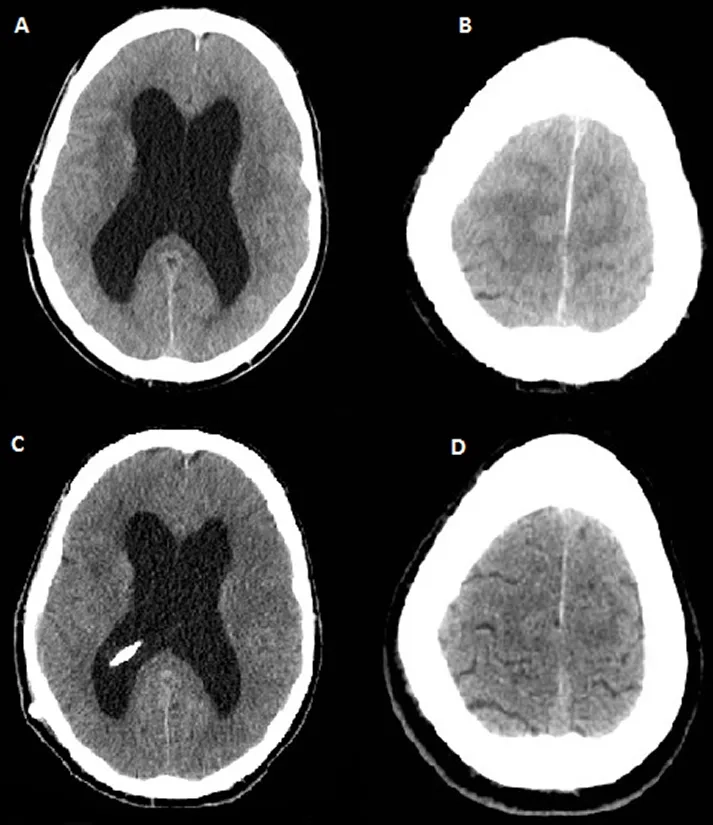

MRI brain scan showing enlarged ventricles in NPH

Understanding hydrocephalus in adults